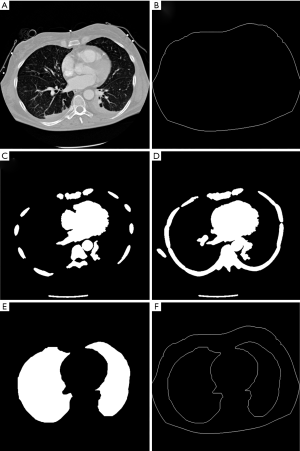

CT images from the same cross-sectional plane between the fourth and the fifth rib as EIT electrodes were analyzed. The thorax contour was determined automatically by thresholding as well as erosion and dilation filtering (18) and described as follow.

- Step 1. The image thresholding technique was used to process the CT image I(x,y) with a threshold value of 800 Hounsfield units (HU) (Figure 1A) and the binary image B(x,y) can be obtained,

- Step 2. The binary image B is then eroded by a 3×3 rectangle R

- Step 3. Small connected areas with less than 200 pixels in the resulting image Be are removed using connected component analysis (8-neighborhood connectivity), producing another binary image Be,o. Further, the image Be,o is dilated by a disk D (radius=5)

Wiener filtering was first applied to the CT images to remove noise. Subsequently the HU of the CT images were rescaled to a range between 0 and 1. The ribs were segmented based on a threshold value of 0.85 since bones have higher density values than other structures. The following morphological operations were further performed to obtain ribs. First, to exclude noise and other non-rib structures, small connected areas with less than 200 pixels are removed using connected component analysis (connectivity=8). Second, to enhance the rib regions, a morphological dilation with a 3×3 disk-shaped structuring element was applied. Third, to form complete rib regions, the holes stemming inside all rib regions were filled by a hole-filling algorithm. Finally, the ribs in one CT image were identified clearly (Figure 1C).

To determine the thoracic cavity, a number of consecutive CT scans near the plane of EIT electrodes were merged after having been processed by the above operations (Figure 1D). Depending on the thickness of CT slices, the number of merging can be varied from 7–15 CT scans. Exploiting the advantage of anatomic knowledge, the 120×120 pixels in the central area of the image (which mainly consist of heart and trachea) were masked as non-rib areas. Further, small connected areas with less than 900 pixels were eliminated using connected component analysis (connectivity=8) to remove non-rib areas inside and outside the thoracic cavity. Next, morphological closing with a radius of 30 pixels disk-shaped structuring element is employed to fill the small holes within the rib areas, closing the gaps between the unclosed rib areas and smooth the edge of rib area, and then the image C only containing rib circle was obtained. Finally, the identification of thoracic cavity was achieved by subtracting the image Cfe after performing morphological filling and erosion (3×3 rectangle) for image C from the image Ce after applying performing erosion (3×3 rectangle) to image C. Further, the contour of the thoracic cavity was determined by using morphological edge detection algorithm for binary images.

Eliminating organs other than lung tissue within thoracic cavity

HU of the original CT image on the EIT electrodes plane were rescaled to a range between 0 and 1. The organs other than lung tissue in the thoracic cavity were identified based on a threshold value of 0.75 of the rescaled HU. In order to avoid classifying collapsed lung tissue into removed organs, the identification process was constricted to the central region of the thoracic cavity. According to the anatomical information and the statistical results of our previous segmentation, the area with 192×212 was selected to segment organs other than lung tissue, such as heart, bronchi and trachea. After thresholding, the morphological operation of removing H-connected pixels was applied to separate different areas because there are many bronchial structures in this selected area. Subsequently, connected areas with less than 100 pixels were removed using connected component analysis (connectivity=8) because these small areas often correspond to the bronchi. Further, the holes stemming close to the center of the thoracic cavity were filled by a hole-filling algorithm because these holes are often caused by the trachea. At the end, these organs other than tissue were eliminated by subtracting them from the segmented thoracic cavity and the lung regions were identified (Figure 1E). The contours of the lungs were determined by using morphological edge detection algorithm (Figure 1F).